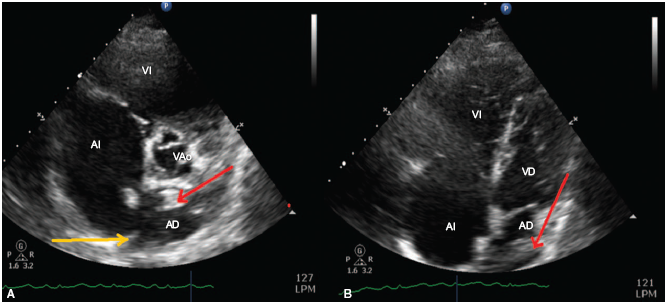

En urgencias, se sospechó tromboembolismo pulmonar (TEP), confirmandose por ecocadiograma transtoracico, el foramen oval evidencio ecodensidad cilíndrica de 60 mm de longitud y 14 mm de diámetro pasando activamente por el foramen (trombo cabalgado) con al menos 30mm de esta estructura ya ubicados en la aurícula izquierda, ver Tabla 1 y Figura 1. Adicionalmente, con miembro inferior izquierdo asimétrico, confirmándose por dopler, trombosis venosa profunda (TVP) poplítea izquierda. Cirugía Cardiovascular realiza trombectomia y cierre foramen ovale con tiempo quirúrgico de 180 minutos (min), bajo circulación extracorpórea de 71 min y clamp de 47 min. Cardioplejia sanguínea. Monitoreo hemodinámico invasivo y catéter arteria pulmonar. Sangrado 500cc. Temperatura 34°C. Se inició óxido nítrico por hipertensión pulmonar supra sistémica, ver Tabla 2. Hallazgos quinirgicos, un gran trombo de 50mm longitud por 10mm ancho, el 80% del mismo se alojaba en aurícula izquierda, anclado al septum pasando a través del foramen ovale, ver Figura 2. Se monitoriza bienestar fetal con doppler continuo. Al ingreso a UCI, paciente con soporte ventila-torio, vasopresor, inotrópico e inodilatador. Fetocardia 120 latidos/minuto, llenado capilar mayor a 4 segundos. 48 horas después, se confirma por ecografía la ausencia de fetocardia. Después de 18 horas, durante el parto presenta un sangrado de 2000 ml, se activa el código rojo, manejo con cristaloides, transfusión de 4 unidades glóbulos rojos y colocación de balón uterino de Bakri para taponamiento uterino, igualmente se administra oxitocina, metilegono-vina y misiprostol 400 mg intrarectal. Al cabo de 48 horas, se retira balón uterino. Evolución favorable en su perfil hemodinámico y gasimétrico, permitiendo el retiro del soporte multisistémico ver Tabla 2. La estrategia ventilatoria invasiva se desarrolló con éxito por 5 días utilizando un modo ventilatorio asistido controlado, presión positiva al final de la inspiración (PEEP) de 8, con fracciones inspiradas de oxigeno altas (100%) durante las primeras 24 hrs con utilización de óxido nítrico.

Figura 1 Ecocardiograma transtoracico. A. Corte para esternal. B. Corte cuatro cámaras. Aurícula derecha (AD), aurícula izquierda (AI), ventrículo derecho (VD), ventrículo izquierdo (VI), Válvula aortica (VAo),foramen ovale permeable (flecha amarilla), trombo (flecha roja).